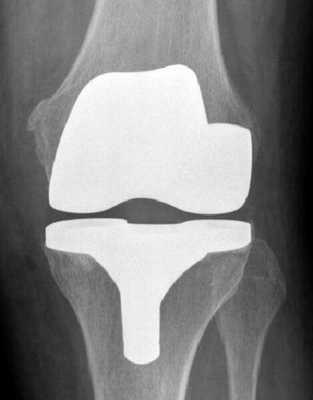

Макет импланта коленного сустава.

Рентген после операции. Протез стоит корректно.

Но вам также необходимо понимать, что устройство, замещающее естественный орган, представляет собой кинематическую конструкцию из металла или керамики с полимерными вставками. Как и любой механизм, такое протезное приспособление требует грамотного использования, чтобы его материалы преждевременно не износились, а подвижные элементы скоротечно не вышли из строя по причине нерациональных нагрузок. Поэтому пациенту нужно позаботиться о том, чтобы эндопротез прослужил исправно как можно дольше. Для этого нужно неукоснительно следовать следующим рекомендациям: